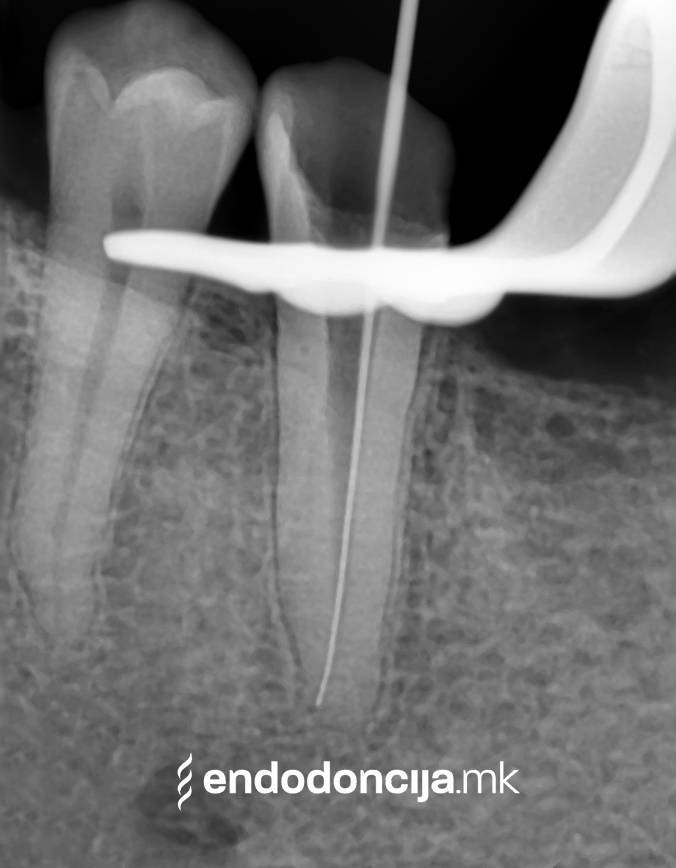

Εκτός από την ανίχνευση των ριζικών καναλιών, η ενδελεχής προετοιμασία και η απολύμανση του ριζικού σωλήνα είναι η προϋπόθεση για μια επιτυχημένη συνολική θεραπεία. Μέσω της χρήσης των νεότερων οργάνων και αντιβακτηριακών διαλυμάτων, όλα τα υπολείμματα ιστών και τα βακτήρια που υπάρχουν μπορούν να εξαλειφθούν.

Οι υπηρεσίες του Ειδικού Τμήματος Ενδοδοντικής δεν περιορίζονται καθόλου στη συμβατική επεξεργασία ριζικών καναλιών. Αντιμετωπίζουμε αποκλειστικά τους ασθενείς μας με τα νεότερα υλικά και όργανα με μικροσκόπιο, προκειμένου να είμαστε σε θέση να καθαρίσουμε εντελώς και να προετοιμάσουμε όλα τα κανάλια πριν τα γεμίσουμε.